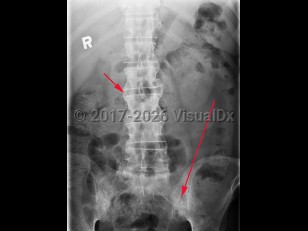

Ankylosing spondylitis is an autoimmune inflammatory disorder characterized by inflammation of the axial skeleton and peripheral joints. It typically begins in the second or third decade of life with a male-to-female prevalence of 2-3:1. There is a high concordance of ankylosing spondylitis in patients with haplotype human leukocyte antigen B27 (HLA-B27).

Patients most typically present with dull pain in the lower lumbar or gluteal region accompanied by early morning stiffness that improves with activity but not with rest. As the disease progresses, pain becomes persistent and bilateral and may worsen at night. Cervical ("chalk-stick") fractures may occur, especially after trauma. In addition to back pain, enthesitis (tenderness at the tendon or ligamentous insertion site to bone) may be common at the costosternal junction, spinous processes, iliac crests, greater trochanters, ischial tuberosities, tibial tuberosities, and heels. Approximately 30% of patients experience arthritis of peripheral joints other than the hips and shoulders. The most common extraarticular manifestation is acute anterior uveitis in up to 40% of patients. A large percentage of others may have inflammation of the terminal ileum or colon, although the majority of cases are asymptomatic. Only a minority of these patients progress to develop inflammatory bowel disease.